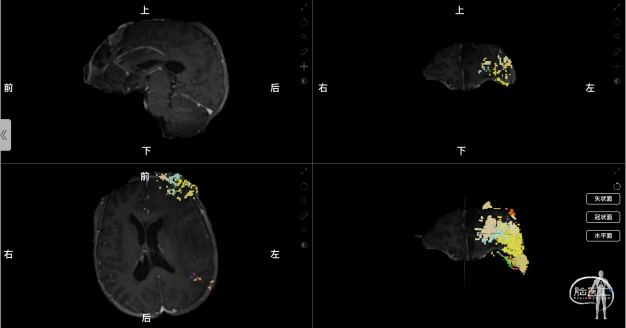

术前采用Nura Surgical脑网络重建分析

使用解剖像磁共振数据+DTI成像,基于Nura Surgical的独特算法追踪全脑的白质纤维束,并使用技术进行个体化的大脑重新分区,生成关键大脑结构网络。根据肿瘤与关键白质纤维束及功能网络的关系,确定收到肿瘤影响最为严重的大脑结构网络为中央执行网络,受到肿瘤影响最为严重的关键关键白质纤维束为皮质脊髓束。其中,中央执行网络的额叶部分与肿瘤关系密切,分布在肿瘤的外下方,应考虑在手术中进行保护。皮质脊髓束没有受到肿瘤直接影响,但受到肿瘤引起的水肿导致患者皮质脊髓束明显被推挤向后移位,预估术后可部分恢复,对患者运动功能影响不大。

图3:术前利用Nura Surgical重建肿瘤与白质纤维束的关系,彩色线条示皮质脊髓束,(左图:可见患侧皮质脊髓束受到瘤周水肿压迫向后移动且密度减低;右图:单独显示的皮质脊髓束结构)